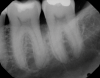

Fig 1. Tooth No. 19 at presentation, buccal view.

Figure 1

Fig 4. Periapical radiograph revealing a distal intrabony defect at tooth No. 19.

Figure 4

In the case presented, a 56-year-old healthy nonsmoking male patient, diagnosed with periodontitis stage III, localized, grade B, had been under care in a private practice periodontal office (RAL) for 25 years. He had a history of good compliance with his treatment (full-mouth plaque score <20%). During the COVID-19 pandemic, the patient missed three supportive periodontal therapy (SPT) visits over a year, resulting in periodontal breakdown interproximal between teeth Nos. 18 and 19 (mandibular left second and first molars, respectively). At his most recent periodontal maintenance visit, significantly increased periodontal probing depths of up to 10 mm with bleeding on probing were noted (Figure 1 through Figure 3). The periapical radiograph revealed a deep, narrow three-wall intrabony defect at the distal aspect of tooth No. 19, with class I buccal furcation involvement (Figure 4). According to the periodontal risk score (PRS),15 formerly known as the Miller-McEntire periodontal prognosis index, the tooth prognosis at the patient's initial examination was "good" (score = 5), taking into account that he was unaware of his hemoglobin A1C (HbA1c) levels. This scoring motivated the patient to be tested, and his follow-up HbA1c was <6%, thus reducing his PRS to 3, which was considered "excellent," as the PRS target goal for regenerative procedures is a score of <5.15